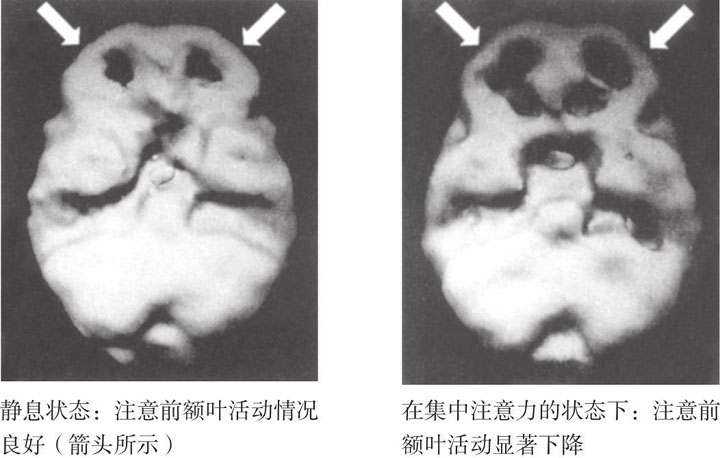

因为已经有了长达9个月的婚姻咨询经验,所以当我看到他们大脑成像结果的时候,就立刻想到了结果的临床意义(见图1-4)。实际上,我因为自己没早点儿想到给他们做脑成像检查而有点儿生气。从成像结果上看,贝齐的扣带回表现出了非常明显的过度激活,这导致她的注意力转移存在一定的障碍,而这种注意力转移上的障碍会导致她总是固执地执着于某一件事情或某一个想法。她的大脑激活模式决定了她总是反复纠结同一件事情,而鲍勃的激活结果则完全不同。在静息状态下,他的大脑表现得很正常,而当他开始集中注意力的时候,大脑的额叶部分却完全没有激活反应(见图1-5)。可是,在人们集中注意力的时候,额叶区域的激活程度应该变强。所以他在注意力集中上存在问题,也很难把注意力放到贝齐身上,或者说,他越是想关注贝齐,反而越没法把注意力集中到贝齐身上。他只能用反其道而行之的方法来让自己的大脑工作起来。鲍勃行为上的症状和他的大脑成像结果很明显地说明,他和他的孩子们一样都患有注意力缺陷障碍。这一点儿都不奇怪,因为注意力缺陷障碍往往是遗传性的。

图1-5 鲍勃受到注意力缺陷障碍影响的大脑立体成像图